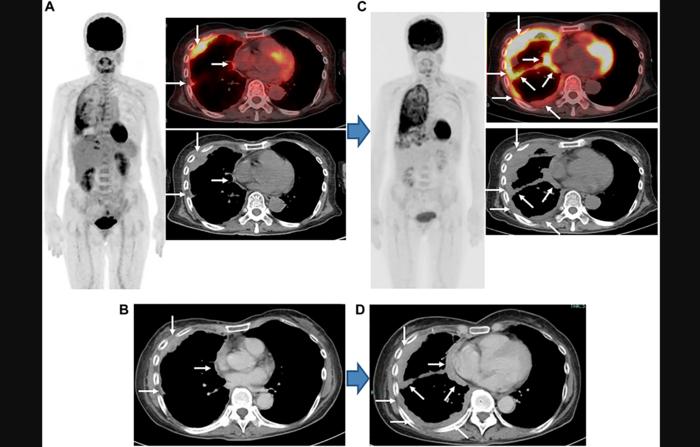

Figure 2: Epithelioid MPM, stage IIIB (cT4N0M0), woman, 64 years old.

Credit: 2024 Kitajima et al.